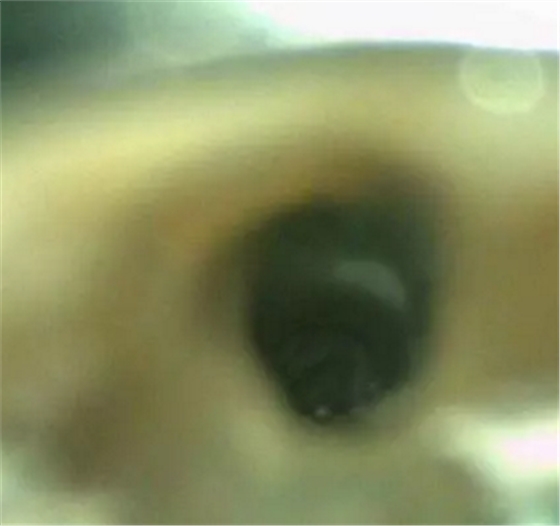

診斷:左上中切牙牙根內(nèi)吸收。治療計劃:左上中切牙根管治療,全冠修復。 治療過程:患者知情同意。使用含1/100,000腎上腺素的4%鹽酸阿替卡因(碧蘭麻,艾龍)局部浸潤麻醉,橡皮障隔濕。去腐未盡露髓,露髓孔出血多。開髓,使用10#不銹鋼K銼(MANI,日本)探查根管,根管中段有鈣化物阻擋,不能達到牙根全長(圖3A)。在顯微鏡下(Leica M400E,萊卡, 德國) 使用超聲尖(E1根管治療超聲尖,啄木鳥公司,中國)通開,采用根管長度測量儀(Root ZX, Morita公司,日本)加診斷絲片法(圖1B)測量根管長22 mm。使用控制扭矩馬達(X-smart,登士柏)和鎳鈦旋轉器械(Hero 642, Micromega)根管預備,根管預備過程中使用5.25%次氯酸鈉溶液沖洗。 根備完成后使用超聲蕩洗根管,5.25%次氯酸鈉溶液3 分鐘, 17% EDTA溶液1分鐘。干燥根管,使用螺旋充填器根管內(nèi)封氫氧化鈣糊,氧化鋅丁香油水門汀暫封。1周后患者復診,患者述無術后不適,檢查暫封完好,無叩痛,不松,牙齦無紅腫瘺管。使用橡皮障隔濕,去除暫封物,超聲蕩洗根管,5.25%次氯酸鈉溶液3 分鐘, 17% EDTA溶液1分鐘。干燥根管,牙膠尖(達雅鼎,中國)和必蘭根充糊劑(Cortisomol, 艾龍公司,法國)熱垂直加壓法根管充填。術后片顯示根充恰填,可見牙膠/糊劑被壓入鈣化物周圍和內(nèi)部縫隙內(nèi)